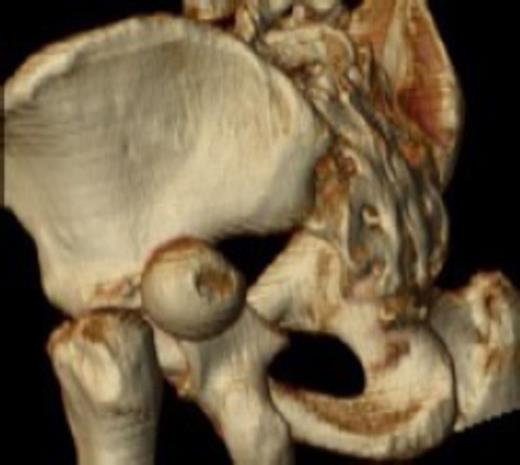

Posterior dislocation of the femoral head with no associated acetabular fracture

Antero-posterior radiograph of the pelvis confirmed a displaced transcervical femoral neck fracture with associated dislocation of the femoral head. Computed-tomography, confirmed a posterior dislocation of the femoral head with no associated acetabular fracture (Fig. 1,2,3).